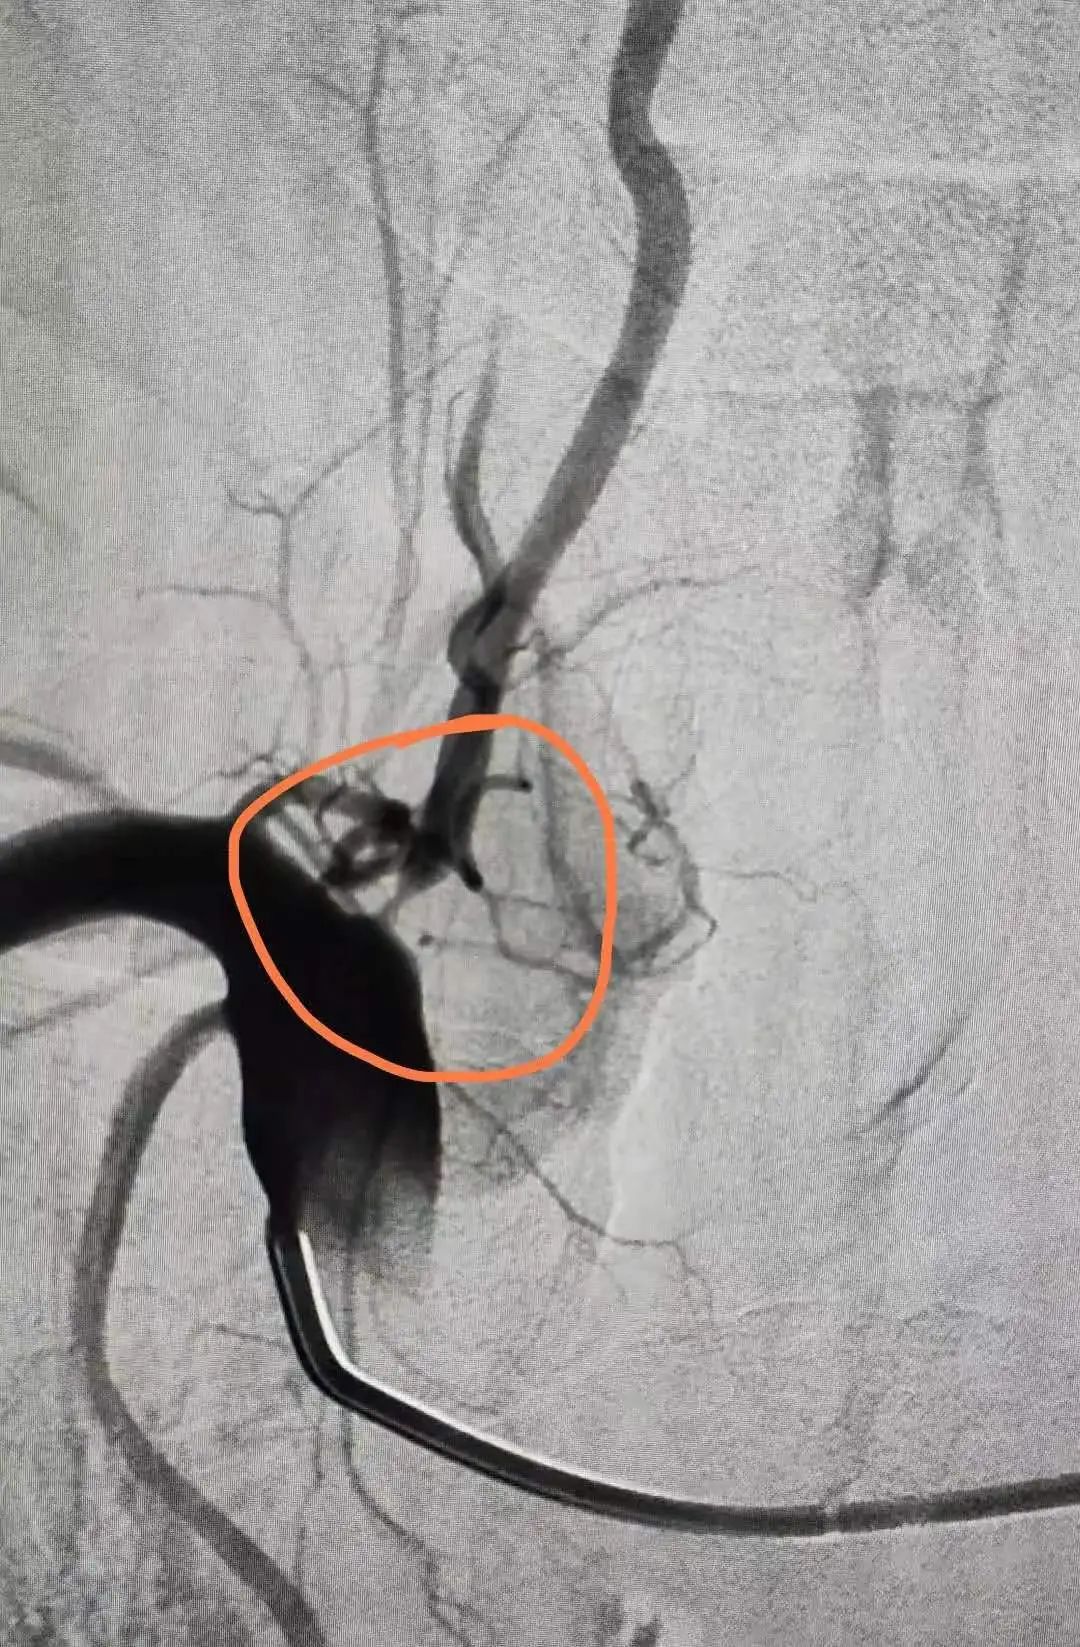

本次患者为中年男性,间断性头晕数年,既往有糖尿病病史,头颈部CT血管造影检查(简称CTA)显示右椎动脉重度狭窄。

术前CTA显示右椎动脉重度狭窄